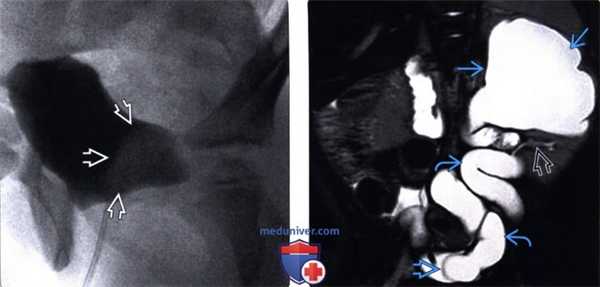

(Левый) При микционной цистоуретрографии визуализируется округлый дефект наполнения в мочевом пузыре, указывающий на уретероцеле.

(Правый) На фронтальном Т2-взвешенном МР срезе визуализируется удвоенная система левой почки с расширенной верхней лоханкой и сдавливанием нижней лоханки/ Верхняя лоханка переходит в значительно расширенный и извитой мочеточник? оканчивающийся внутрипузырным уретероцеле.